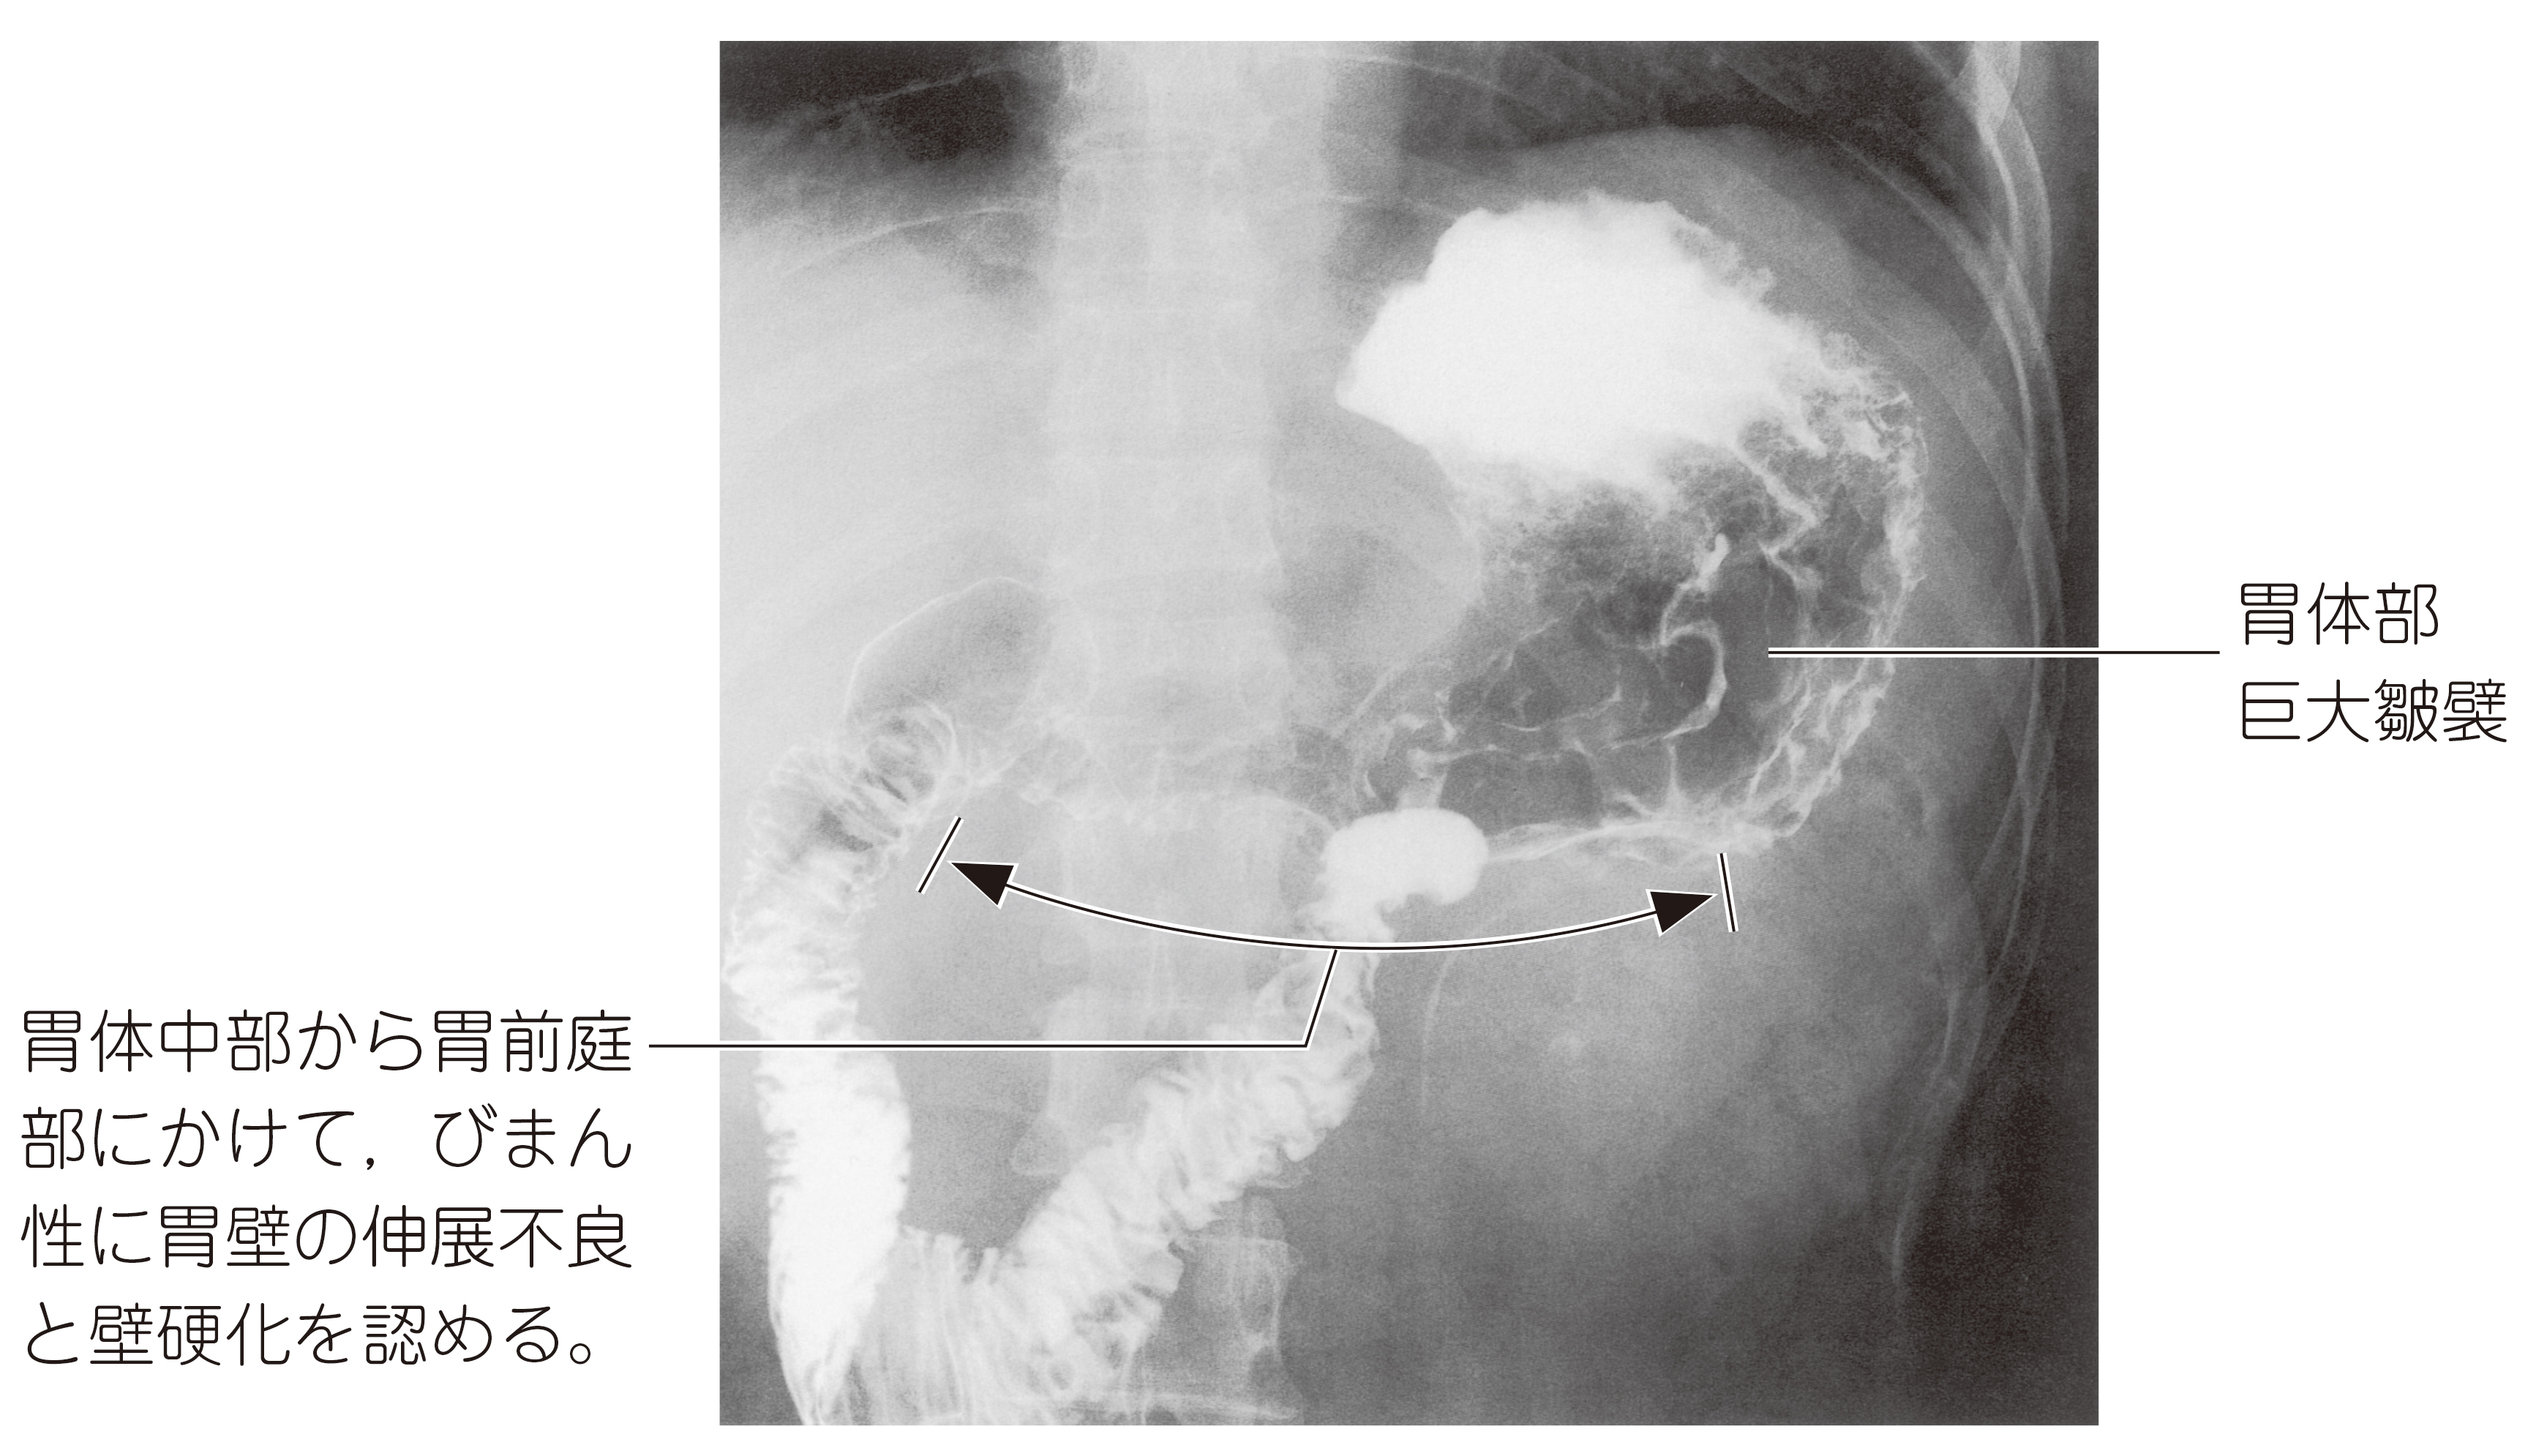

32歳の女性。急激な体重減少を主訴に来院した。6か月前から心窩部痛を自覚している。腹部は膨隆し,波動を認める。肝・脾を触知しない。穿刺腹水所見:淡黄褐色,総タンパク4.0g/dL。血液所見:赤沈4mm/1時間,赤血球344万,Hb 9.8g/dL,Ht 28%,血小板6万,プロトロンビン時間70%(基準80~120),フィブリノゲン100mg/dL(基準200~400),FDP 28μg/mL(基準5以下)。血清生化学所見:総タンパク6.9g/dL,アルブミン3.5g/dL,AST 30U/L,ALT 22U/L,LDH 719U/L(基準176~353),ALP 230U/L(基準260以下)。CEA 5.5ng/mL(基準5以下)。上部消化管造影写真を示す。

画像診断

上画像参照。